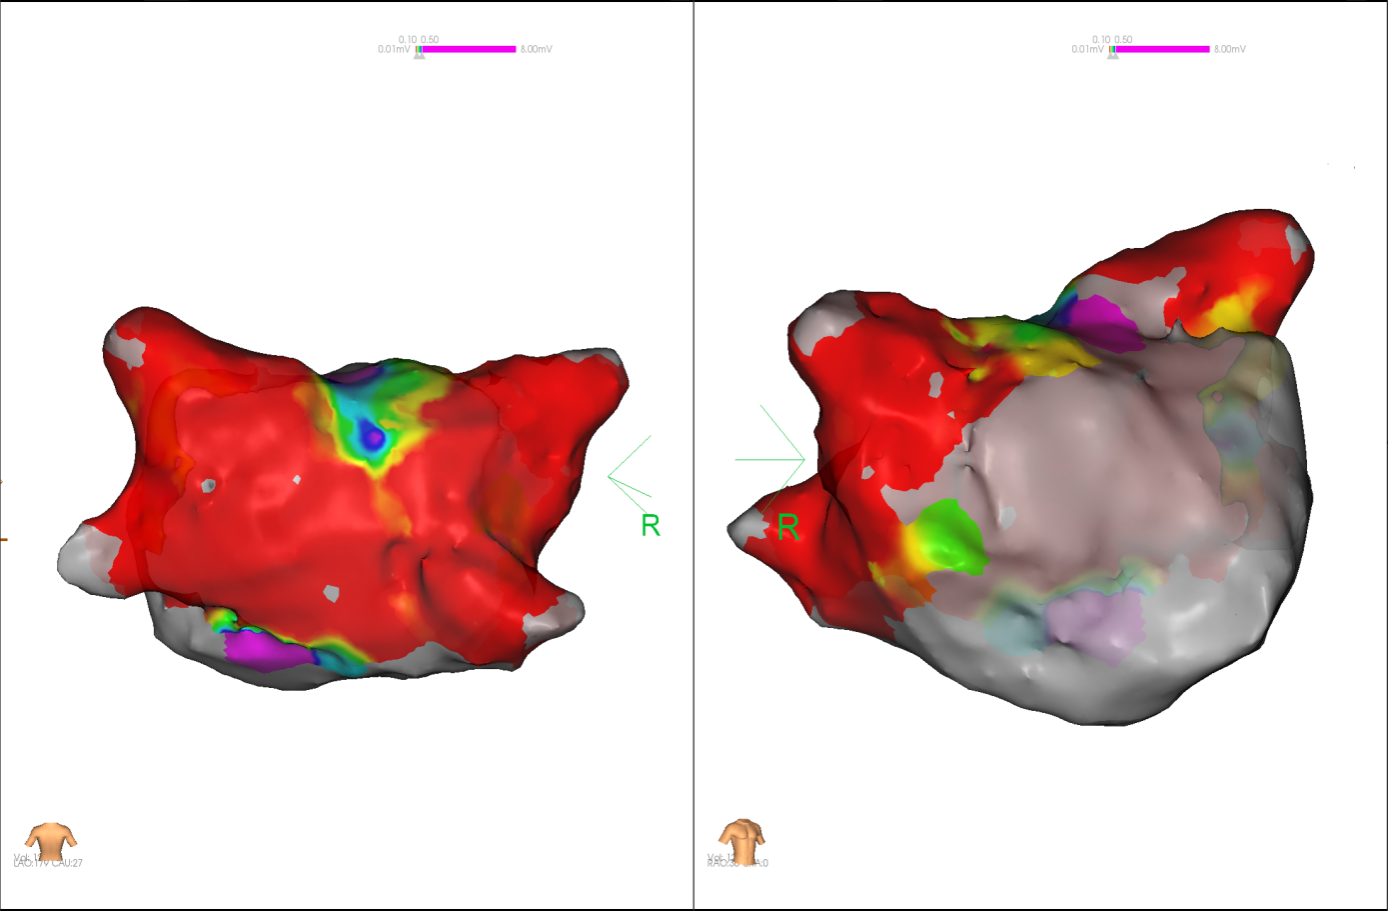

图4 消融前后基质标测提示肺静脉消融效果明显

图2 术中电压标测提示左房基质差

经充分术前评估及准备后,该患者手术在抗心衰药物持续静脉泵入、高流量吸氧支持下及麻醉、护理团队的通力配合下进行,由薛建颖、崔明亮主治医师具体实施。术中通过右侧股静脉送入心腔内超声至右心房,排除左房血栓后成功指导房间隔穿刺,沿可调弯鞘管送入锦江心脏脉冲电场消融导管至左房,构建左房三维解剖模型并行基质标测,标测显示左房基质差,分别行左侧、右侧肺静脉及后壁BOX消融。消融参数:1800v,400ms,400μs,共放电消融140次(消融右肺静脉时转复为窦性心律),验证双肺静脉均隔离。术后重新标测显示所有肺静脉均已急性阻滞,消融效果理想,肺静脉前庭损伤范围也达到了预期的标准,同时心腔内超声监测未见明显心包积液。手术仅用时30分钟,时间明显缩短,手术过程精准高效。术后患者恢复情况良好,维持窦性心律。